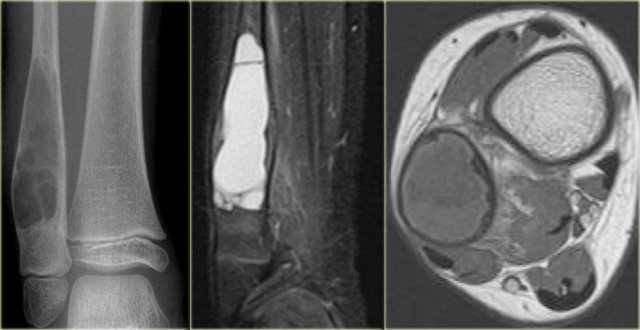

Here a patient with arthrosis of the knee and a large well-defined osteolytic lesion in the epiphysis of the tibia.

In young patients the differential diagnosis would include chondroblastoma, intraosseous ganglion and giant cell tumor.

In this elderly patient with arthrosis this lesion is most probably a degenerative cyst.